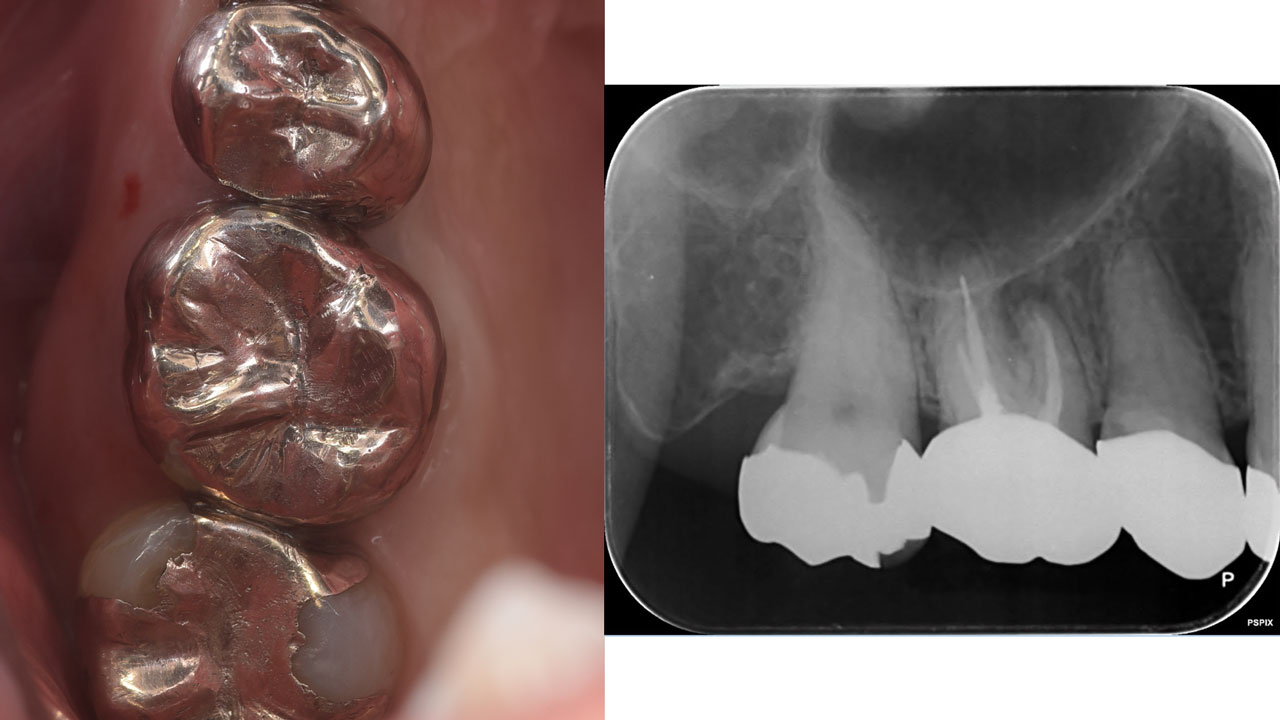

ワイド・ショートインプラントの基礎と臨床 完全版裁断済みです。表紙のダメージは多いですが、中は書き込みマーキング以外の汚れは少ないです。裁断位置が左側ページ文字ギリギリになっています。ご了承の上お取引お願いします。- タイトル: ワイド・ショートインプラントの基礎と臨床 完全版- 林揚春 ご覧いただきありがとうございます。